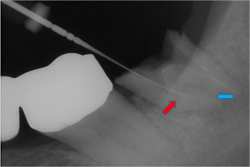

根管治療レッジ除去リカバリー症例

術前 ➡

術中

根の先に影(感染)が出てしまい根の治療を行わないといけないのですが以前他院にて処置を施した古い薬が入っています

画像を見ると手前の根にはしっかりと先まで薬が入っていません(1枚目の画像)

根のカーブに対応できず間違った方向へ削り込んでしまっています(赤矢印)

古い薬を除去しとあるテクニックを駆使し正しい根幹への道を見つけました(青矢印)

簡単にやっているように見えますがそのまま器具を入れては大きく間違った道に導かれてしまうなか、その脇から1mmにも満たない狭く曲がった孔を探しそちらへ導くのは至難の技ですが、マイクロスコープとCTを使いしっかりとした手法で行うとこのような症例にも対応できます